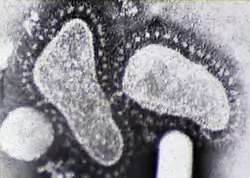

Orthocoronavirinae, comúnmente conocidos como coronavirus, es una subfamilia de virus ARN monocatenario positivos perteneciente a la familia Coronaviridae. Se subdivide en los géneros Alphacoronavirus, Betacoronavirus, Gammacoronavirus y Deltacoronavirus.[2][3] Estos incluyen genogrupos filogenéticamente similares de virus con una nucleocápside de simetría helicoidal con envoltura cuyos viriones pueden medir entre aproximadamente 50 y 200 nm de diámetro. Su material genético es el de mayor tamaño dentro de los virus de ARN, con genomas que van desde los 26 a 32 kilonucleótidos.[4][5] Se les llama coronavirus por la corona de puntas que se ve alrededor de la superficie del virus. Fue descrito por primera vez en 1965.[6]

Las partes que conforman la estructura general de los coronavirus son, como en todos los virus animales, la envoltura y la nucleocápside. En el caso de los coronavirus, en la envoltura se encuentra una glucoproteína de membrana (M) de 20 a 35 kDa, que forma una matriz en contacto con la nucleocápside. Además se encuentra en la envoltura la glucoproteína S, de 180 a 220 kDa,[23] que forma las espículas, espigas o peplómeros responsables de la adhesión a la célula huésped. En el caso específico del coronavirus SARS, en sus espículas un dominio de unión para receptores definidos dirigen la adherencia del virus a su receptor celular, la enzima convertidora de angiotensina 2 (ACE-2).[24] Algunos coronavirus (específicamente los miembros de Betacoronavirus subgrupo A, también llamado subgénero Embecovirus[25]) tienen también en la superficie una proteína adicional más corta llamada esterasa-hemaglutinina.[26]